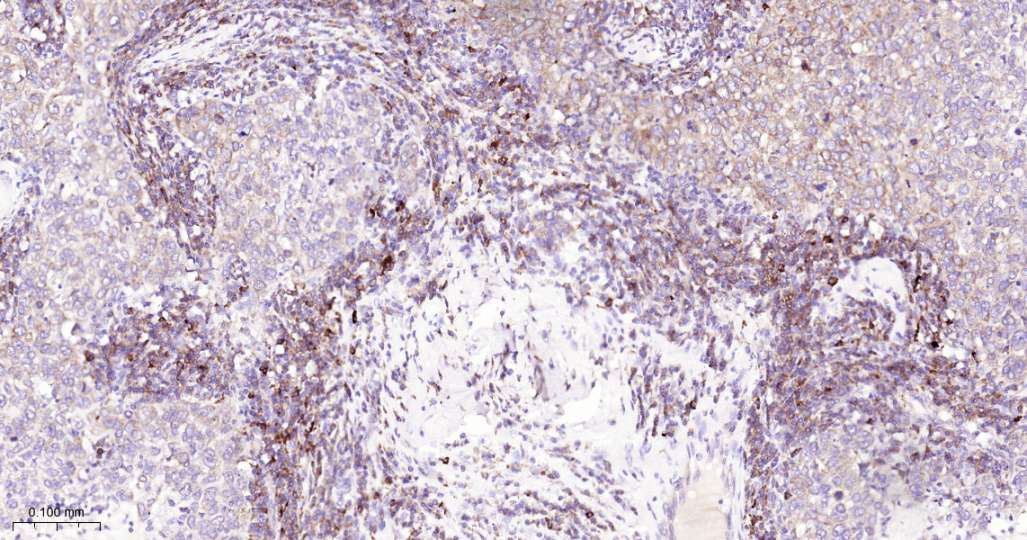

Immunohistochemical analysis of paraffin embedded Mouse colon tissue slide using IHC0645 (EIF2S1 Kit).

Immunohistochemical analysis of paraffin embedded Human breast cancer tissue slide using IHC0645 (EIF2S1 Kit).

Immunohistochemical analysis of paraffin embedded Human colon cancer tissue slide using IHC0645 (EIF2S1 Kit).

Immunohistochemical analysis of paraffin embedded Rat colon tissue slide using IHC0645 (EIF2S1 Kit).